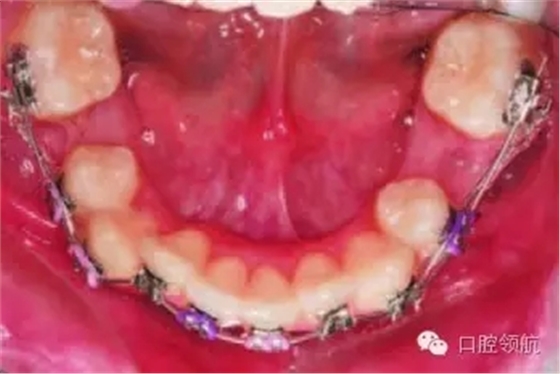

尖牙代替?zhèn)惹醒赖姆椒ǎ和ㄟ^正畸方法將尖牙移動(dòng)到側(cè)切牙的位置,再經(jīng)局部漂白、調(diào)磨改形或全冠修復(fù),恢復(fù)側(cè)切牙形態(tài)。正畸醫(yī)生要考慮的問題有:尖牙與切牙齦緣高度是否一致,尖牙是否需要腭側(cè)控根。通過直接粘結(jié)具有根腭向轉(zhuǎn)矩的托槽,或者將具有根唇向轉(zhuǎn)矩的托槽反粘,配合使用全尺寸弓絲(0.021英寸×0.025 英寸),以實(shí)現(xiàn)尖牙的腭側(cè)控根(圖3.5)。對牙尖的調(diào)磨應(yīng)逐次進(jìn)行,以最大限度地減少對牙髓的刺激,避免出現(xiàn)牙髓鈣化或失活。